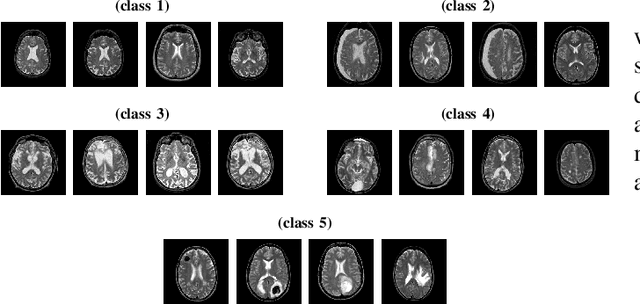

Abstract:Liver Cirrhosis plays a critical role in the prognosis of chronic liver disease. Early detection and timely intervention are critical in significantly reducing mortality rates. However, the intricate anatomical architecture and diverse pathological changes of liver tissue complicate the accurate detection and characterization of lesions in clinical settings. Existing methods underutilize the spatial anatomical details in volumetric MRI data, thereby hindering their clinical effectiveness and explainability. To address this challenge, we introduce a novel Mamba-based network, SRMA-Mamba, designed to model the spatial relationships within the complex anatomical structures of MRI volumes. By integrating the Spatial Anatomy-Based Mamba module (SABMamba), SRMA-Mamba performs selective Mamba scans within liver cirrhotic tissues and combines anatomical information from the sagittal, coronal, and axial planes to construct a global spatial context representation, enabling efficient volumetric segmentation of pathological liver structures. Furthermore, we introduce the Spatial Reverse Attention module (SRMA), designed to progressively refine cirrhotic details in the segmentation map, utilizing both the coarse segmentation map and hierarchical encoding features. Extensive experiments demonstrate that SRMA-Mamba surpasses state-of-the-art methods, delivering exceptional performance in 3D pathological liver segmentation. Our code is available for public: {\color{blue}{https://github.com/JunZengz/SRMA-Mamba}}.